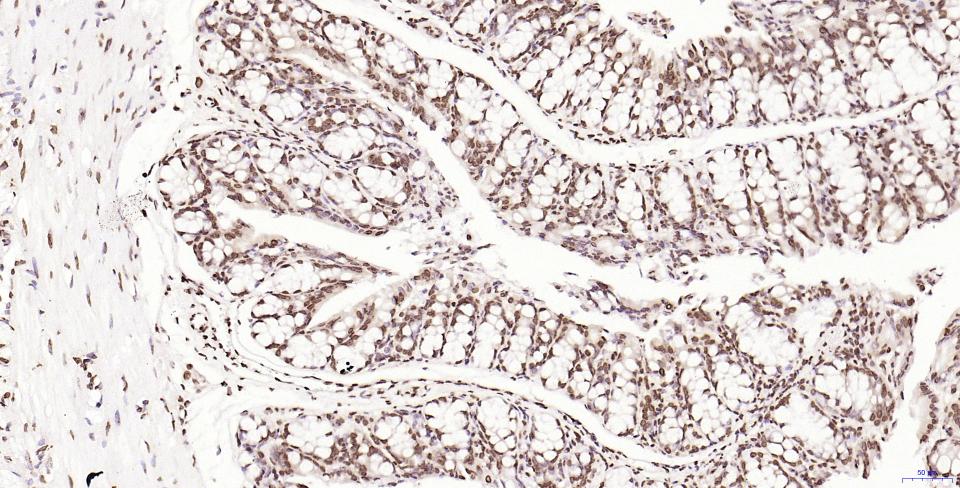

Paraformaldehyde-fixed, paraffin embedded Human Kidney; Antigen retrieval by boiling in sodium citrate buffer (pH6.0) for 15 min; Antibody incubation with Histone H2A.X Monoclonal Antibody, Unconjugated(bsm-61080R) at 1:200 overnight at 4°C, followed by conjugation to the SP Kit(Rabbit, SP-0023) and DAB (C-0010) staining.

Paraformaldehyde-fixed, paraffin embedded Human Colon Cancer; Antigen retrieval by boiling in sodium citrate buffer (pH6.0) for 15 min; Antibody incubation with Histone H2A.X Monoclonal Antibody, Unconjugated(bsm-61080R) at 1:200 overnight at 4°C, followed by conjugation to the SP Kit(Rabbit, SP-0023) and DAB (C-0010) staining.